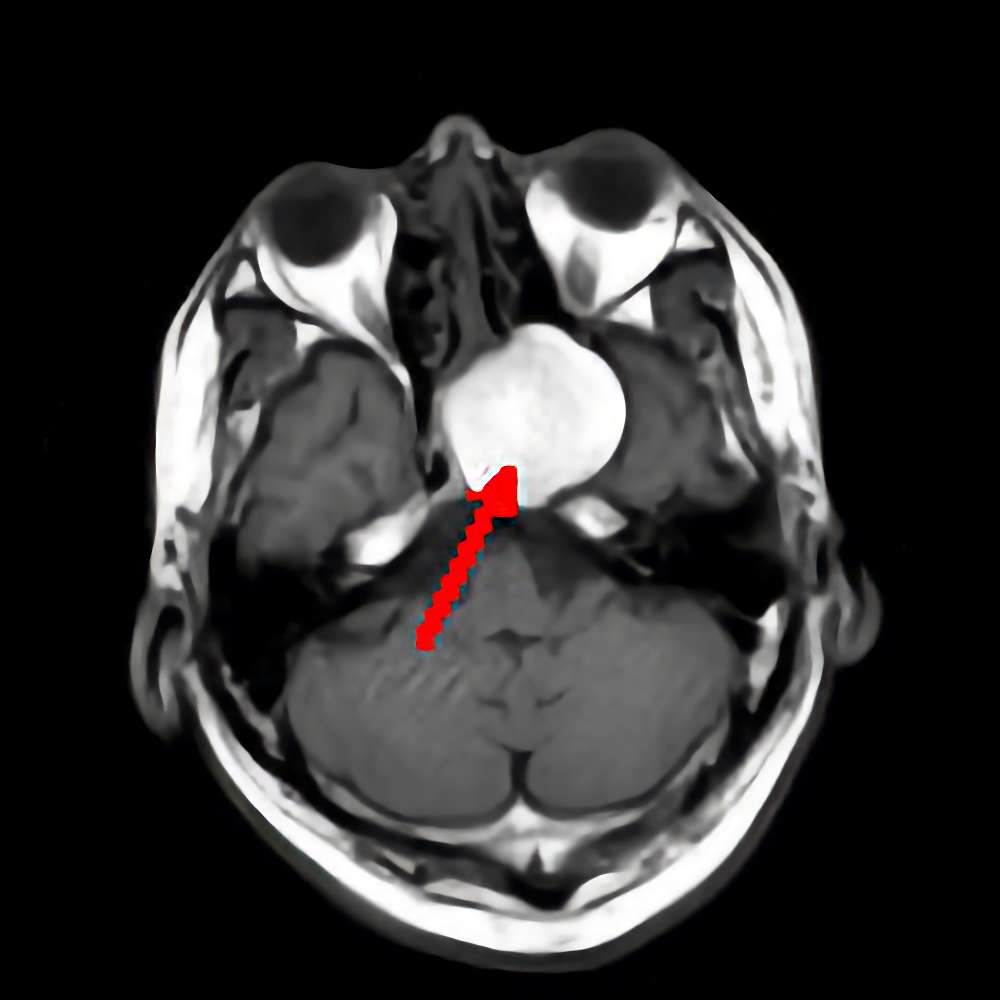

'15年7月

50代

聴神経鞘腫

No.’15_95 手術前1

No.’15_95 摘出 前

No.’15_95 摘出 後